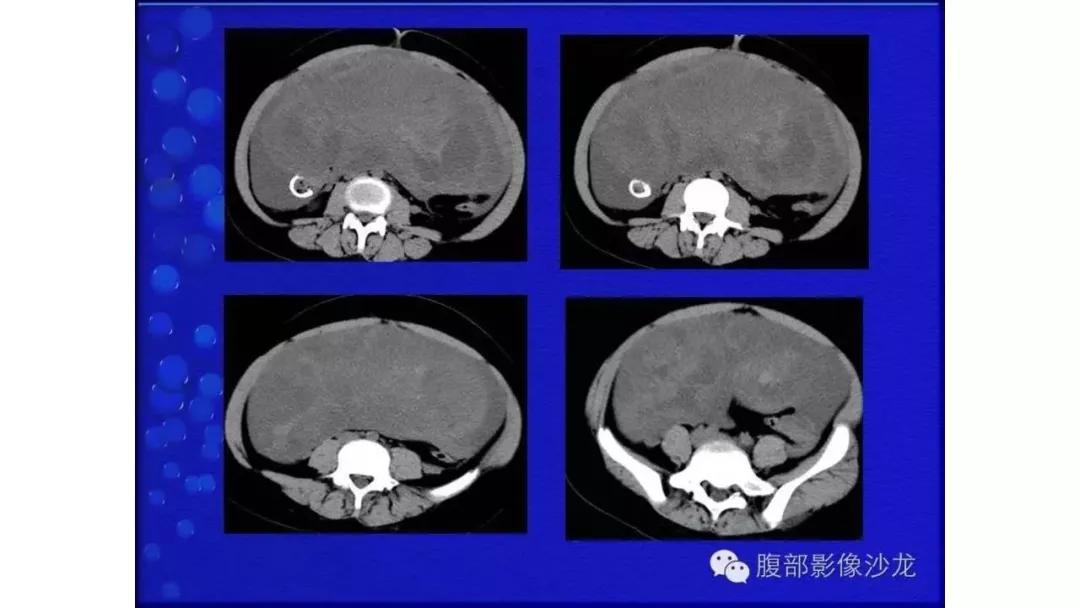

生殖细胞肿瘤占卵巢肿瘤的20%,以成熟畸胎瘤-皮样囊肿多见,良性多,恶性少。表现为囊实性混合性或实性肿块,大多数含有脂肪、钙化等特征。

良性者常呈囊性肿块,脂囊,脂液囊,液囊。少数混合成分,实性。壁光整可稍厚,囊内有脂、液分层现象,多数伴有粗大钙化或骨骼。

出现脂肪:畸胎瘤,囊性为主是成熟、实性为主是不成熟